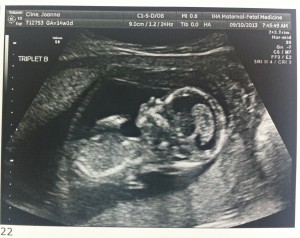

Baby B – is a GIRL!

A is 170 grams, B is 175 grams and C is 178 grams so they’re all measuring well. Grow, grow, grow!